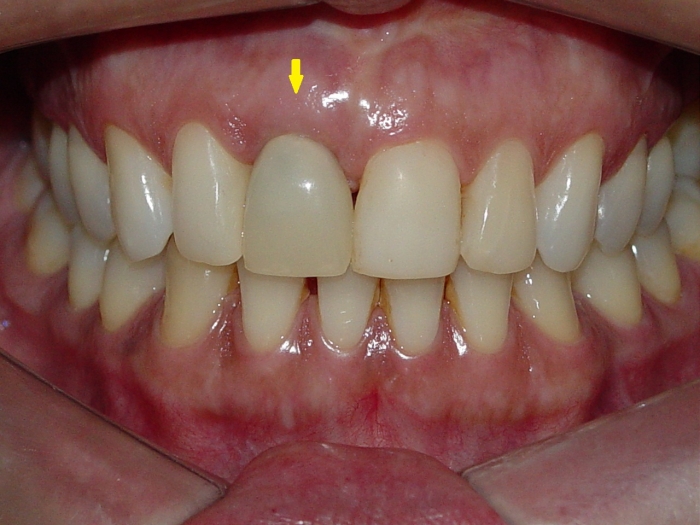

Prótese provisória fixa sobre implante cone Morse